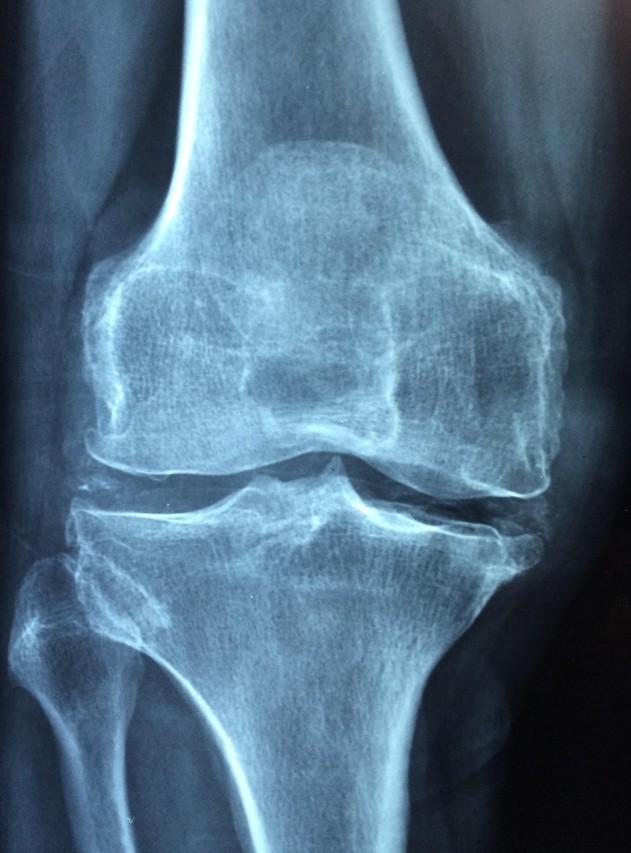

통풍은 체내에 요산(Uric acid)이 과도하게 축적되어 관절에 결정 형태로 침착되면서 발생하는 염증성 질환입니다. 요산은 퓨린(purine)이라는 물질이 대사 되면서 생기며, 이 요산이 신장을 통해 제대로 배출되지 않거나 과잉 생성되면 혈중 농도가 상승하여 통풍 발작으로 이어지게 됩니다. 정상인의 경우 혈액 내 요산 농도는 일정 수준으로 유지되며, 대부분 소변으로 배출됩니다. 그러나 신장 기능 저하, 유전적 요인, 식이습관, 비만, 알코올 섭취 등이 복합적으로 작용하면서 요산의 배출이 원활하지 않거나 생성량이 증가하게 됩니다. 이로 인해 혈중 요산 농도가 7.0mg/dL 이상이 되면 고요산혈증(hyperuricemia) 상태가 되며, 이 상태가 장기화되면 통풍으로 진행될 수 있습니다. 요산 결정은 특히 발가락, 발등, 무릎 등 말단 관절에 침착되기 쉽고, 이 부위에 염증 반응을 일으켜 통증, 부기, 열감 등을 유발합니다. 급성 통풍 발작은 보통 밤중이나 새벽에 갑작스럽게 시작되며, 매우 심한 통증으로 인해 일상생활에 큰 지장을 초래합니다. 따라서 통풍의 근본적인 관리는 단순한 통증 완화에 그치지 않고, 요산 수치를 정상 범위로 조절하는 것이 핵심입니다. 이를 위해서는 퓨린 섭취를 제한하고, 요산 배출을 돕는 식습관과 생활습관이 필수적입니다.